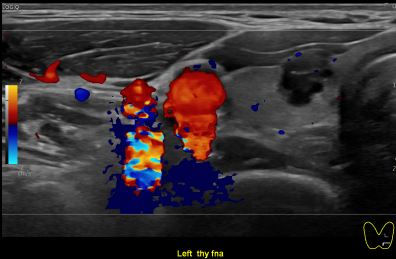

상기환자 외부건진이상소견 정밀검사위해 내원하신 30대중반 여성분으로

의심스러운 갑상선 좌엽 결절 세포검사 진행후 갑상선암으로 진단되었습니다